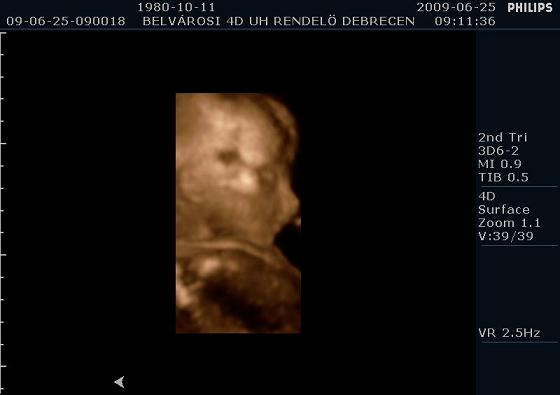

Profilból

Profilból